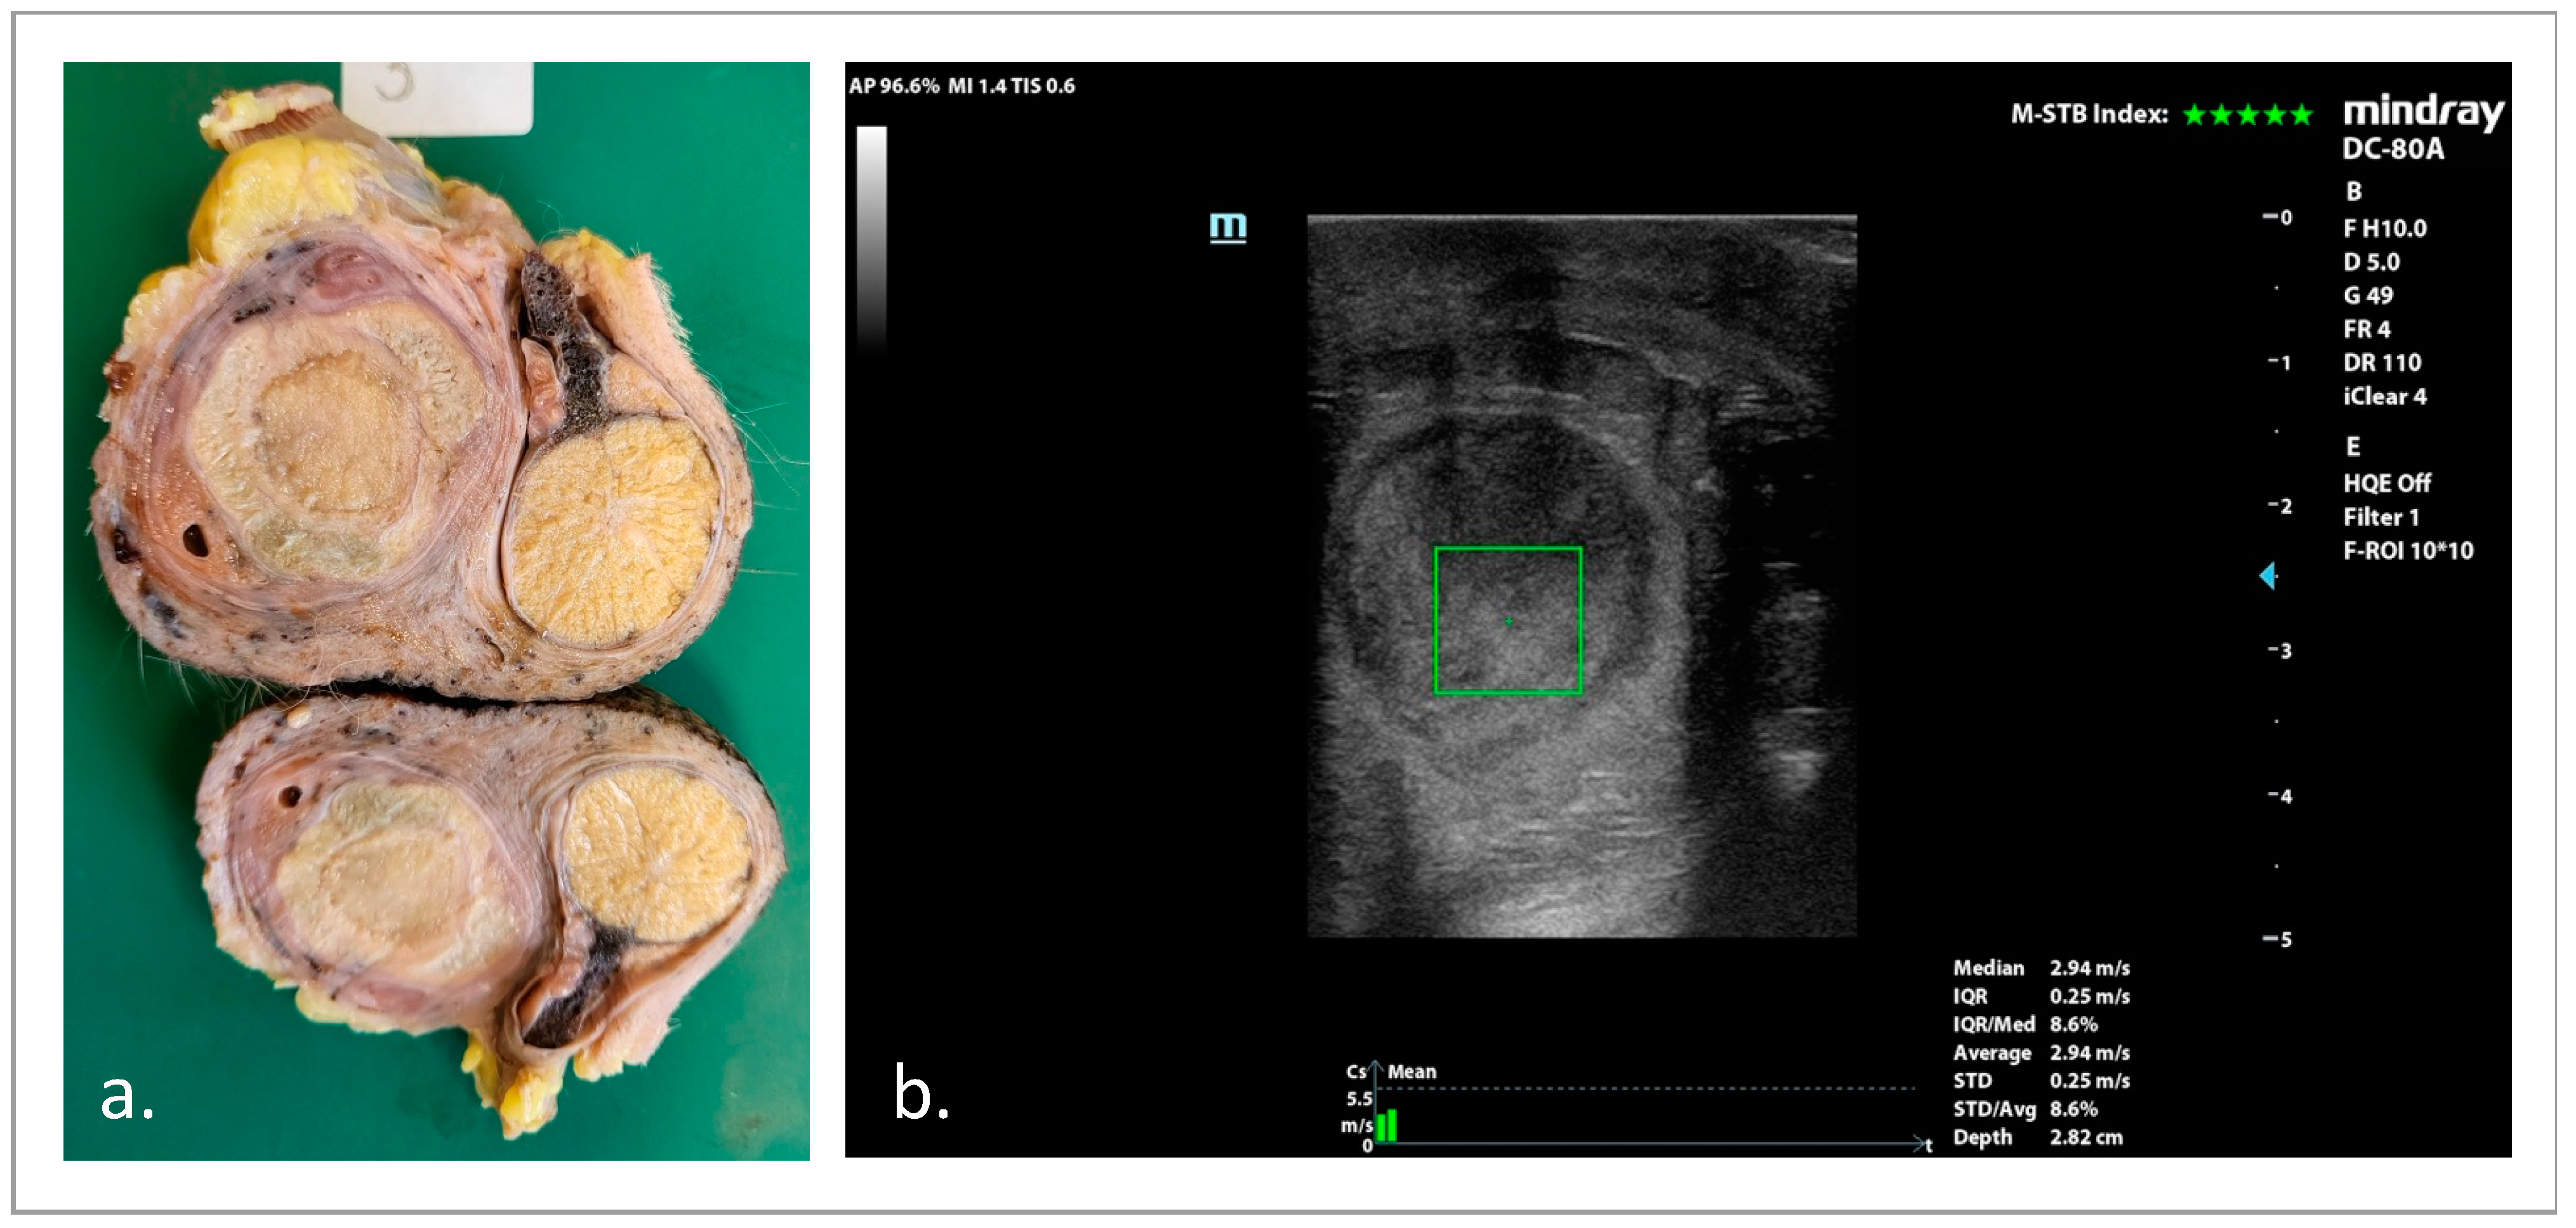

3.4. SWE Examinations

3.4.2. pSWE